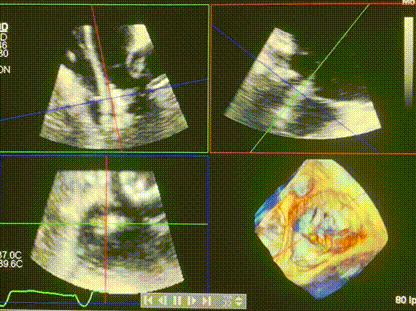

術中輸送器在超聲引導下調整位置

手術在全麻狀態下進行。術者采用經右側頸靜脈入路的方式將輸送器送入患者心臟內,在TEE及DSA引導下調整輸送器頭端角度,使得輸送器與三尖瓣瓣環平面垂直。在輸送器進入右心室后釋放室間隔錨定裝置,而后釋放瓣葉夾持件(2個耳片結構)成垂直狀態。在TEE及DSA確定夾持件固定至三尖瓣葉根部且位于右室側后釋放人工瓣心房側盤片。隨后調整瓣膜同軸性以及室間隔錨定件位置(貼合室間隔),前推藏針管并固定,進而釋放室間隔錨定裝置,并再次確認瓣膜位置、穩定性及同軸性,合攏輸送鞘后撤出輸送器,完成LuX-Valve Plus人工三尖瓣瓣膜的植入,僅殘余微量瓣周漏。且經手術中心電生理團隊評估,病人的起搏器和ICD功能沒有受到影響。

術后超聲顯示僅殘余微量瓣周漏